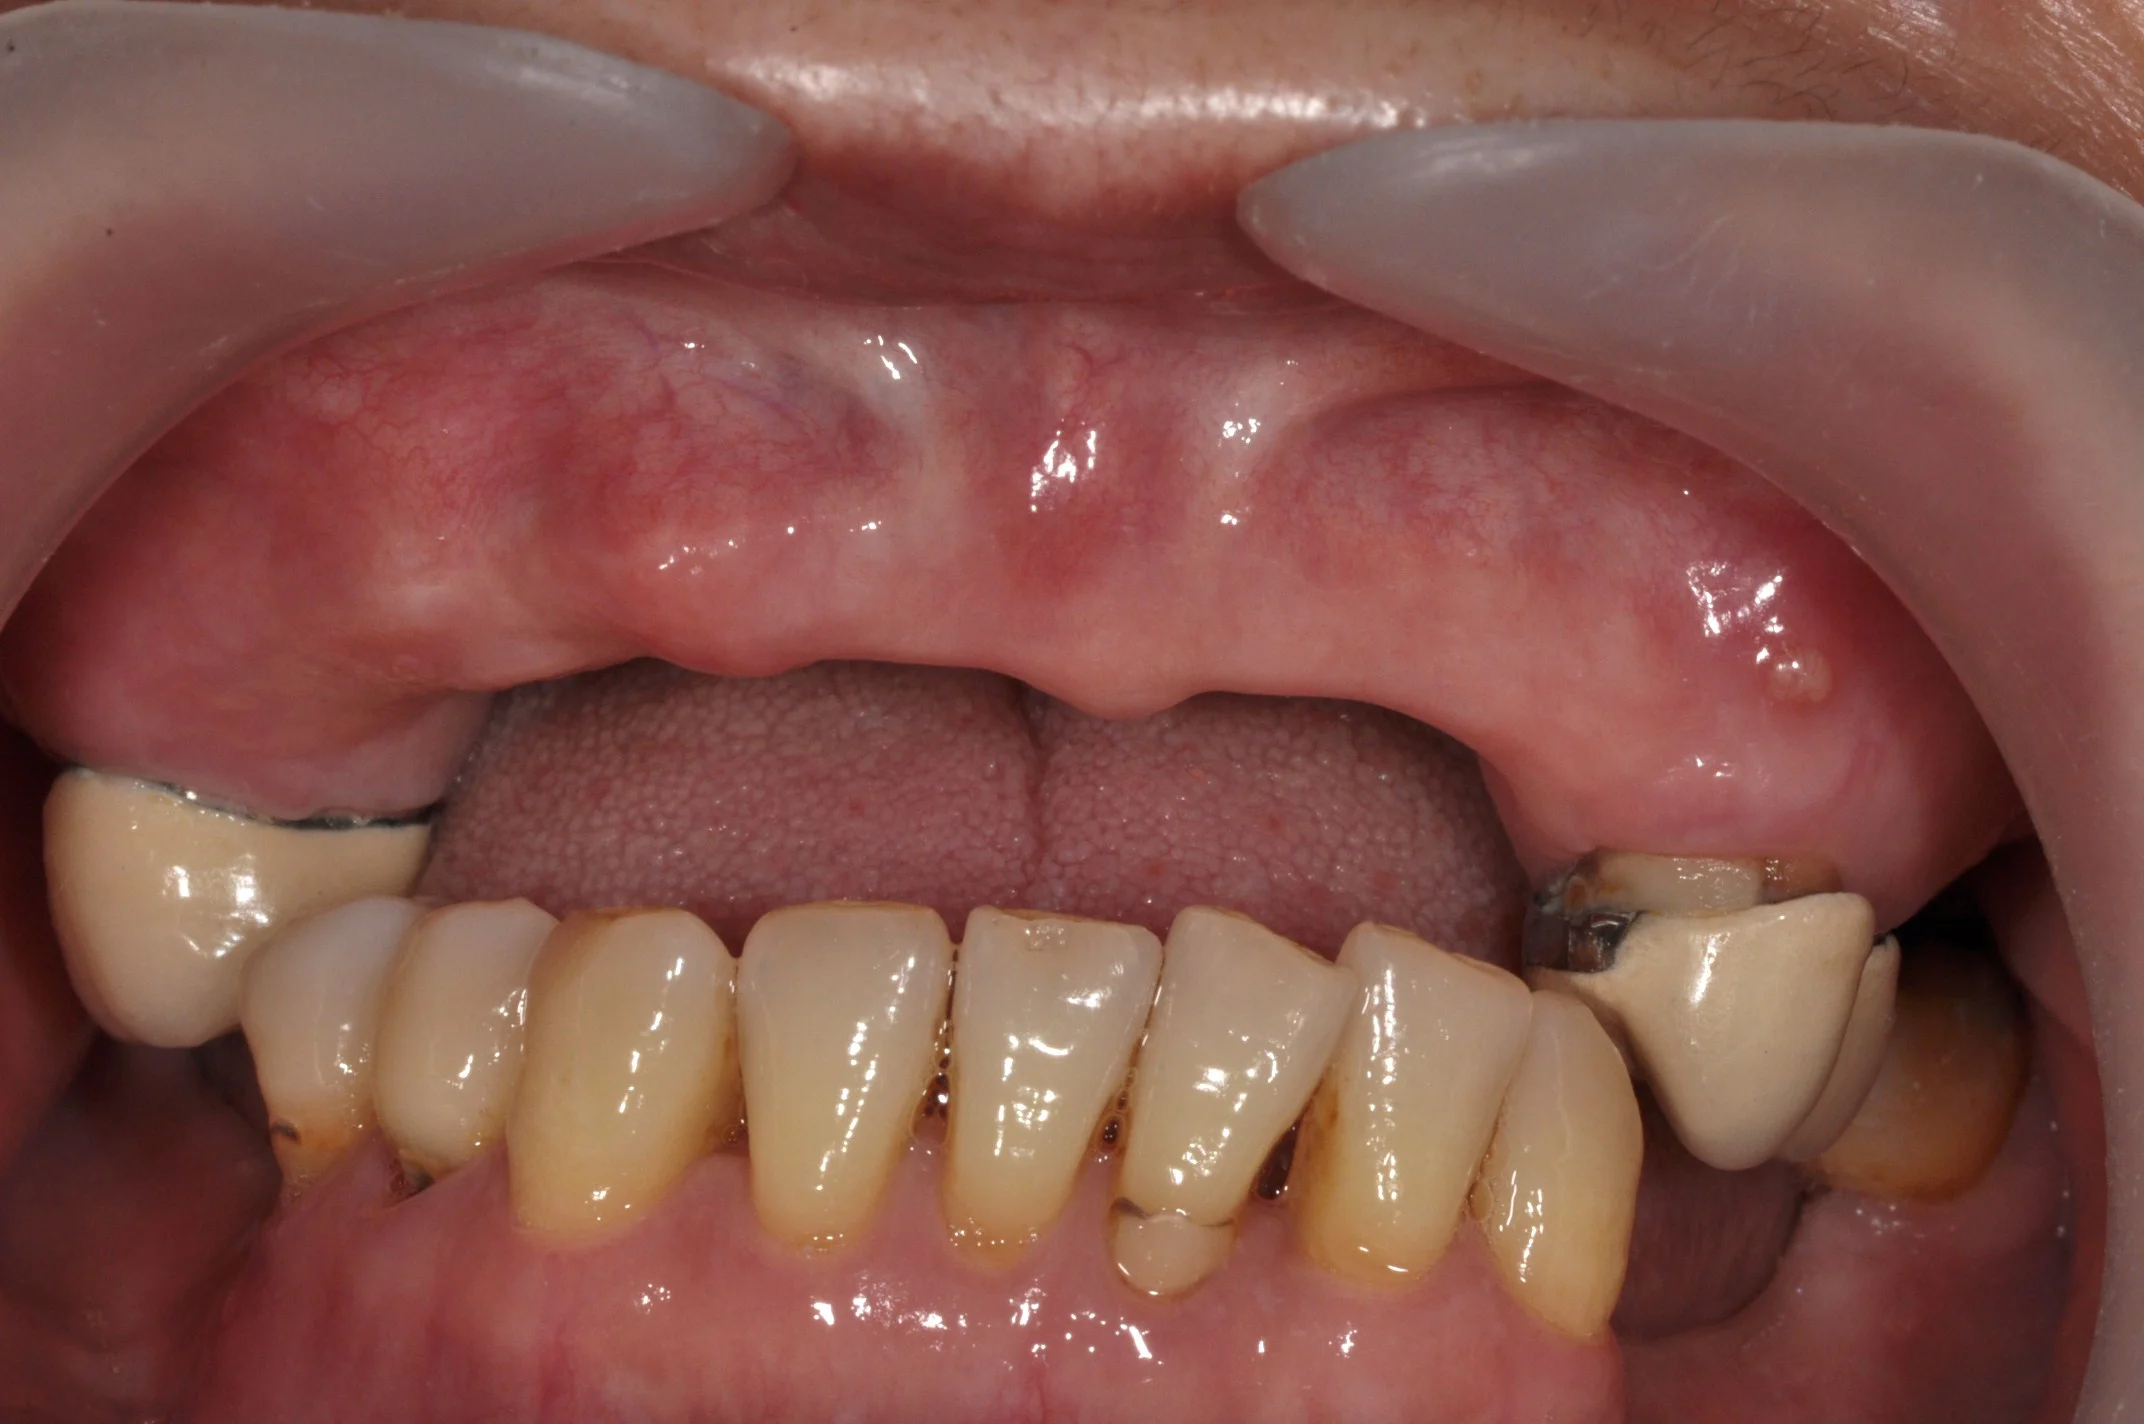

DSC_1011.JPG

BEFORE

SINGLE FRONT TOOTH IMPLANT